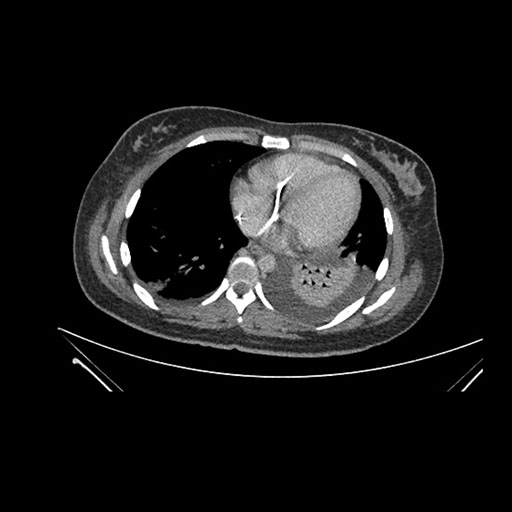

Imaging Analysis

Look through the patient's CT scan to identify any areas of concern for the necessary procedure.

Axial Venous

Based on initial findings, which issue(s) would you be most concerned about?